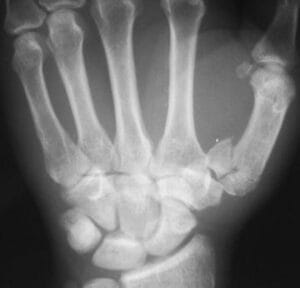

Based on fracture pattern (Figure 2)

- Intra-articular

- Bennett (Figure 1c and d)

Bennett Fracture

- Fracture line into the joint surface

- Palmar ulna fragment held in place by strong anterior oblique (beak) ligament

- Abductor pollicis longus pulls shaft radially and dorsally can leave the joint subluxed/dislocated